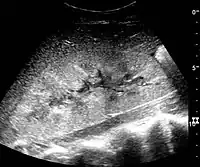

Renal ultrasonograph in renal failure after surgery with increased cortical echogenicity and kidney size. Biopsy showed acute tubular necrosis.[16]

In medical imaging, the acute changes in the kidney are often examined with renal ultrasonography as the first-line modality, where CT scan and magnetic resonance imaging (MRI) are used for the follow-up examinations and when US fails to demonstrate abnormalities. In evaluation of the acute changes in the kidney, the echogenicity of the renal structures, the delineation of the kidney, the renal vascularity, kidney size and focal abnormalities are observed.[16] CT is preferred in renal traumas, but US is used for follow-up, especially in the patients suspected for the formation of urinomas. A CT scan of the abdomen will also demonstrate bladder distension or hydronephrosis.